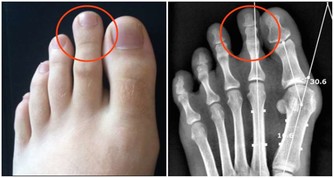

一說起尿毒症可能大家現在都不太陌生,尿毒症是指身體不能通過腎臟產生尿液,把身體代謝所產生的廢物,還有多餘的水分排出體外而引起的毒害,尿毒症是腎功能下降

有疾病放任不管

很多人認為身體出現的是小問題就無關緊要,沒有從根本上解決,隨著疾病的不斷發展,小的問題會逐漸嚴重,

如果意識到正確應對疾病的重要性,